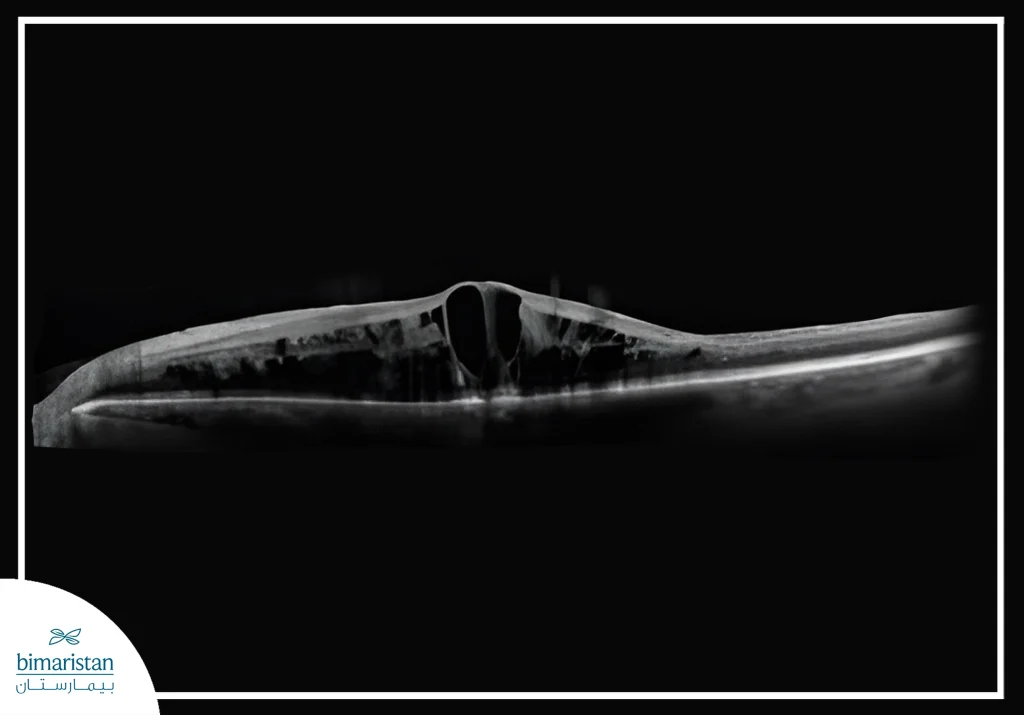

2. التصوير المقطعي للتماسك البصري

عد من أهم الفحوص الحديثة لتقييم الشبكية، يكشف وذمة اللطخة الصفراء الناتجة عن تراكم السوائل في مركز الإبصار ويقيس سماكة الطبقات الشبكية بدقة، ويساعد في متابعة تطور الحالة واستجابة المريض للعلاج بالحقن أو الليزر.